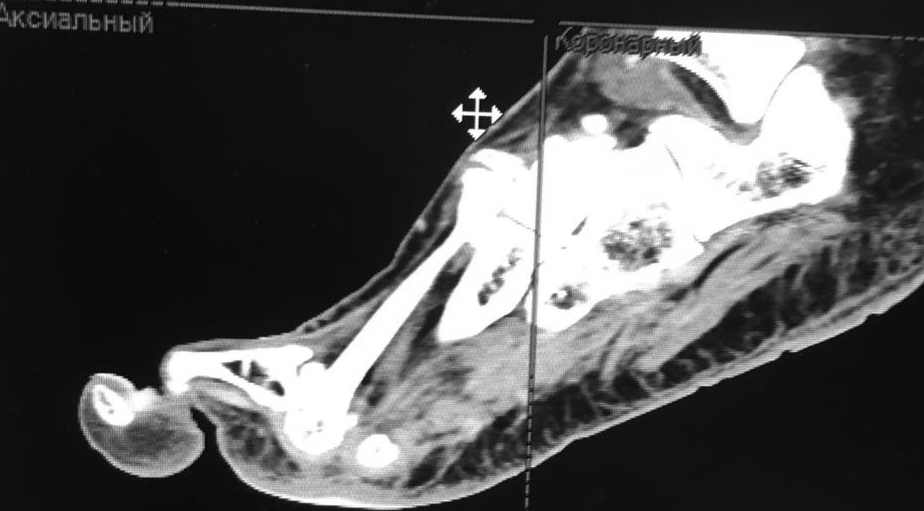

женщина средних лет, оперирована около года назад

Насколько я понял, беспокоит метатарсалгия. Достаточно будет укоротить

II-IV? Что-то другое? на что обратить внимание?